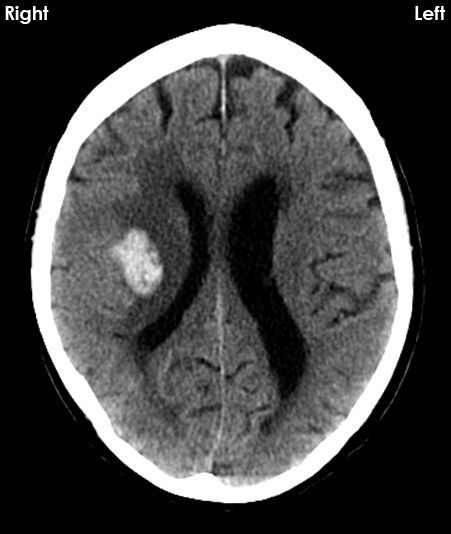

X-RAY QUIZ: Which finding is present on this image?

B: Sail sign

C: Meniscus sign

Start Quiz bit.ly/36i1txn